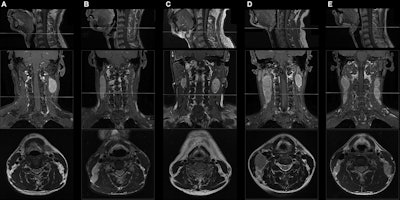

Sagittal T1-weighted fat-suppressed contrast-enhanced MRI scans (top row) show the caudal border of the hyoid bone. Coronal T1-weighted fat-suppressed contrast-enhanced (middle row) and axial T2-weighted MRI scans (bottom row) show the presence or absence of middle neck involvement in five patients with N1 or N2 nasopharyngeal carcinoma (NPC). (A) A 49-year-old male patient with N1 NPC and without middle neck involvement. (B) A 45-year-old male patient with N1 NPC and middle neck involvement. (C) A 49-year-old male patient with N2 NPC and without middle neck involvement. (D) A 30-year-old female patient with N2 NPC and unilateral middle neck involvement. (E) A 19-year-old male patient with N2 NPC and bilateral middle neck involvement.Sagittal T1-weighted fat-suppressed contrast-enhanced MRI scans (top row) show the caudal border of the hyoid bone. Coronal T1-weighted fat-suppressed contrast-enhanced (middle row) and axial T2-weighted MRI scans (bottom row) show the presence or absence of middle neck involvement in five patients with N1 or N2 nasopharyngeal carcinoma (NPC). (A) A 49-year-old male patient with N1 NPC and without middle neck involvement. (B) A 45-year-old male patient with N1 NPC and middle neck involvement. (C) A 49-year-old male patient with N2 NPC and without middle neck involvement. (D) A 30-year-old female patient with N2 NPC and unilateral middle neck involvement. (E) A 19-year-old male patient with N2 NPC and bilateral middle neck involvement. Images and caption courtesy of the RSNA.